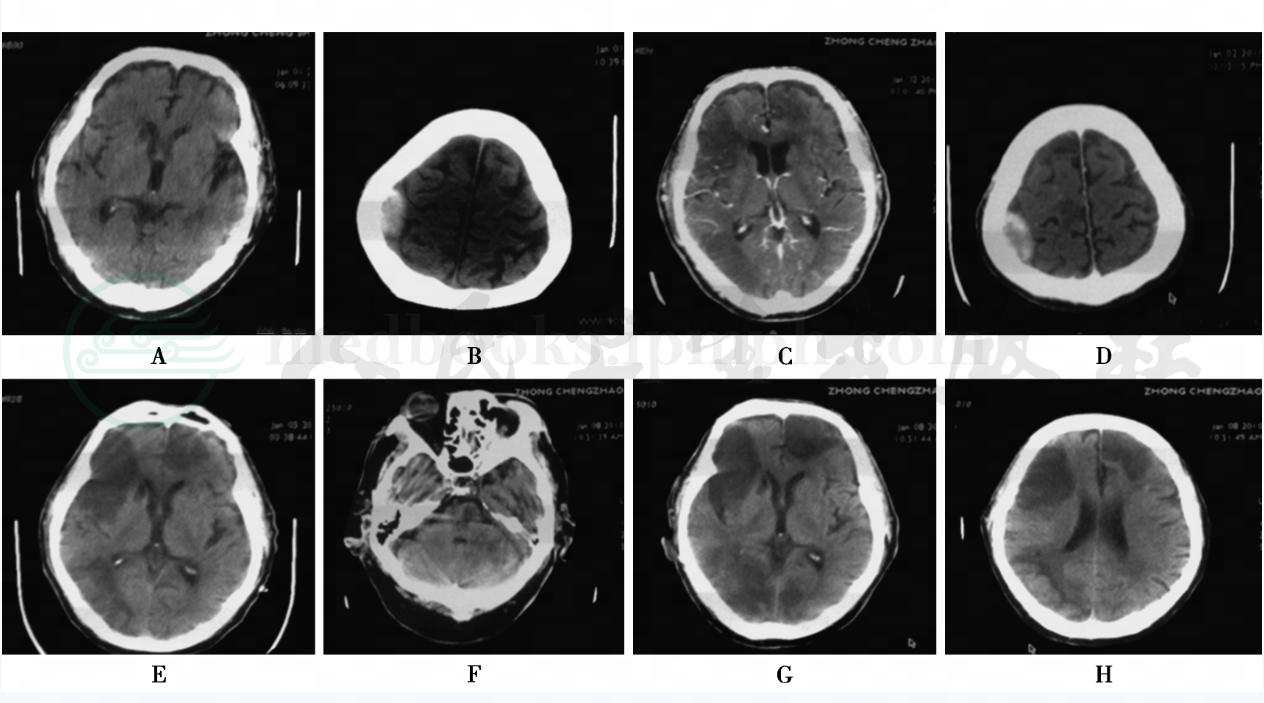

图1 头颅CT

A.1月1日6:09pm;B.1月1日10:39pm;C.1月2日3pm;D.1月2日3pm;E.1月5日3:38pm;F.1月8日10:53am;G.1月8日10:53am;H.1月8日10:53am

2010-1-1(急诊):①右侧顶部可见高密度影,考虑右侧顶部硬膜外血肿(量约4ml),建议复查或增强扫描,排除脑膜瘤;②双侧基底节区多发腔隙性脑梗死;③双侧脑室旁白质脱髓鞘;④脑萎缩。

2010-1-1(复查):与前片对比,现片提示右侧额叶可见斑片稍低密度区,局部脑沟模糊,可疑早期脑梗死,建议复查;右顶部高密度灶大小、形态大致同前。

2010-1-2(增强):与前片相比,双侧额叶及右顶枕叶可见大片低密度无强化区,边缘清楚,有顶部高密度灶明显强化。印象:①双侧额叶及右顶枕叶多发脑梗死;②双侧基底节区可见多发腔隙性脑梗死;③右顶部脑膜瘤。

2010-1-5(复查):与2010-1-2号片相比,双侧额叶及右顶枕叶可见大片梗死灶大小、形态同前,有枕叶梗死灶密度有所恢复。

2010-1-8(复查):与前片对比,左侧枕叶新发斑片状脑梗死灶,双侧额叶及部分右侧枕叶病灶密度进一步降低,左侧小脑半球密度降低,脑梗死?建议复查。